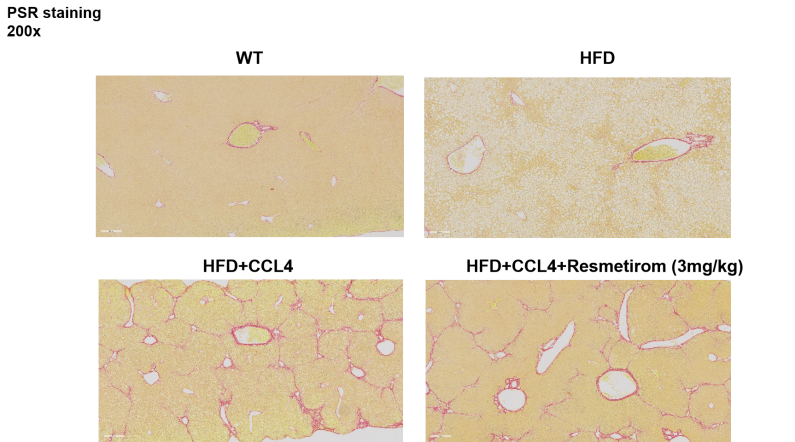

小鼠肝脏病理组织学检测结果:HE染色、ORO染色、PSR染色与NAS评分